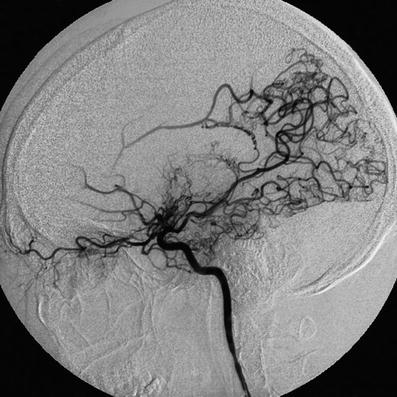

Abb 4 8 Moyamoya Erkrankung Download Scientific Diagram

Diagnostik Und Therapie Der Moyamoya Erkrankung